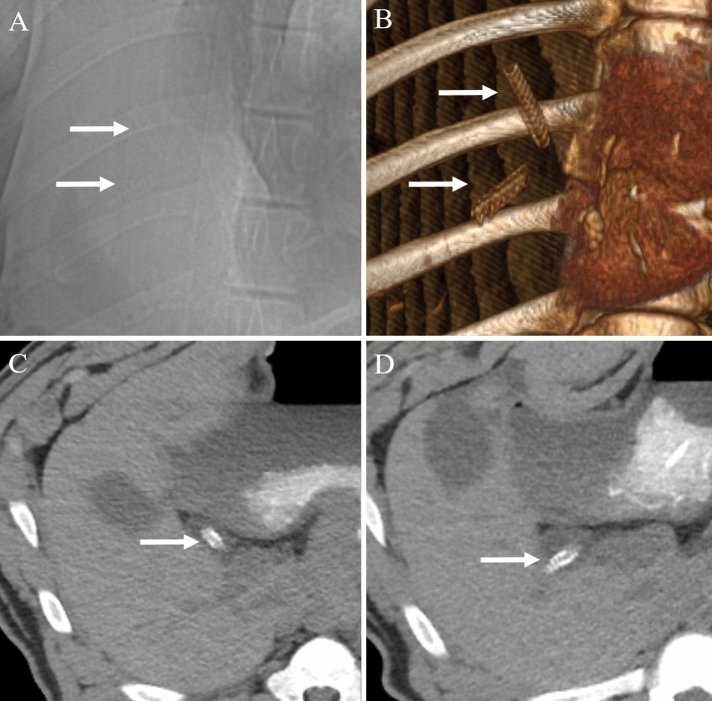

On follow-up non-contrast CT examination, there was no radiologic evidence of bile duct obstruction or leakage in any pig (n = 14). Furthermore, the stents were clearly visualized as radiopaque material, which made it easy to confirm the position and condition of the stents (Fig. 5). Among the six pigs in the stent group with 3-month follow-up, in one pig, the stent disappeared on the 3-month follow-up CT. Of the five pigs in the stent group with 1-month follow-up, two pigs showed disappearance of stents on the 1-month follow-up CT. This might be due to distal migration of the stents following bile duct peristalsis. In addition, among the 11 pigs in the stent group, three pigs in the stent group with 3-month follow-up had a stent fracture on the 2-month follow-up CT (Fig. 6).